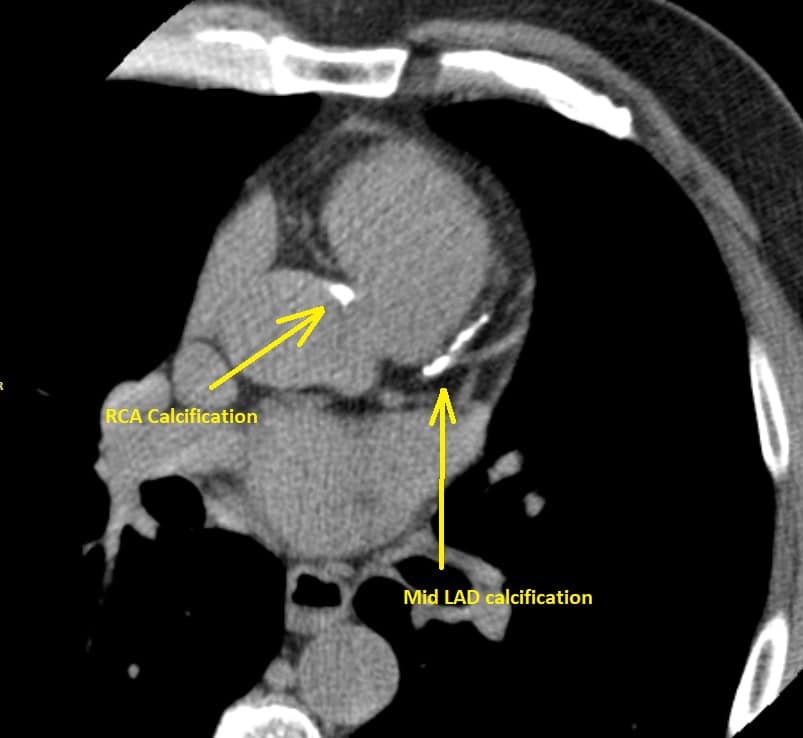

ただし、CAC スコアは基本的にCVDリスクのより正確な見積もりを行うためのツールであり、冠動脈疾患や狭窄の存在を診断するためのものではない。そのため、ほとんどの研究が既存の臨床項目によるリスク予測ツールにCACスコアを追加することによる予測性能の改善を見ており(Lin)、冠動脈疾患や狭窄の存在に対する診断性能(感度、特異度など)について精度の高い研究は少ない。

図はGrundyのfigure2に追記したもの